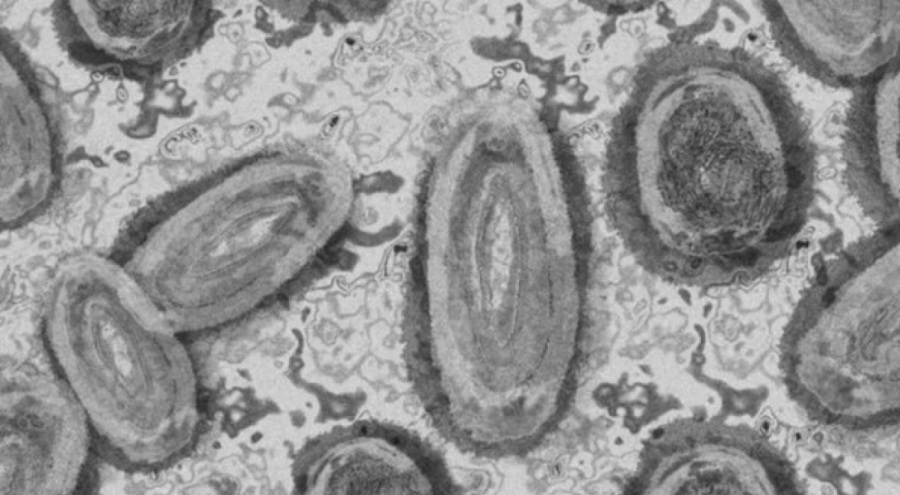

Pekin'de maymun çiçeği virüsü görüldü

Dünya genelinde endişelere neden olan maymun çiçeği virüsü Çin'in başkenti Pekin'de görüldü. Pekin Hastalık Önleme ve Kontrol Merkezi tarafından yapılan açıklamada, yurt dışı kaynaklı bir vaka görüldüğü ve bu vakayla temaslı bir kişide daha virüs tespit edildiği belirtildi.

Yapılan açıklamada virüs bulaşan 2 kişinin hastanede karantinaya alındığı, belediye ve ilçe sağlık kurumları tarafından temaslı takibi yapıldığı kaydedildi. Tedavi altına alınan hastaların durumunun stabil olduğu açıklandı.

Orta ve Batı Afrika ülkelerinde yaygın olarak görülen maymun çiçeği virüsü şuana kadar 111 ülkede tespit edildi. Dünya Sağlık Örgütü (DSÖ) tarafından 11 Mayıs'ta yapılan açıklamada, maymun çiçeği virüsünün yüzde 90 oranında azaldığı ve artık uluslararası öneme sahip bir halk sağlığı acil durumu olmaktan çıkarıldığı ifade edilmişti.

Çiçek hastalığı ile benzerlik taşıyan maymun çiçeği virüsü buluşan hastalarda yüksek ateş, baş, sırt ve kas ağrıları, üşüme ve titreme, ciltte döküntü gibi belirtiler görülüyor.